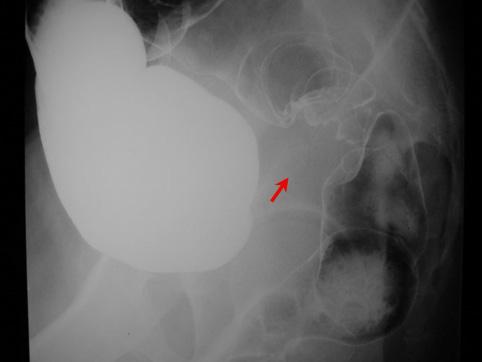

A case of endometriosis of the upper part of the rectum that required a partial resection.

Tumor-like lesions/Endometriosis

Large intestine(Colon)/Rectum

X-ray

40 -